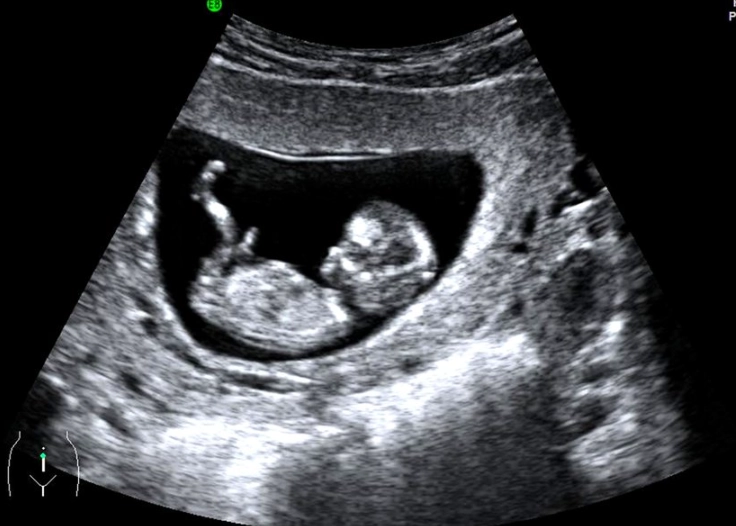

You might have had an earlier scan around 6-8 weeks, maybe to confirm the pregnancy or check the heartbeat. That one's important, sure, but it's often just a little blob and a flicker. The 12 weeks pregnant ultrasound is different. It's the first major, detailed check-up for your baby. Think of it as the end of the first trimester graduation exam.

They'll point things out as they go: "There's the head," "See the heartbeat flickering," "Those are the little arm buds moving." You'll likely see your baby bouncing, stretching, or even sucking its thumb. It's utterly mesmerizing.

This is the headline act. The sonographer will zoom in for a perfect side-profile view of the baby and measure the translucent (fluid-filled) space at the back of the neck in millimeters. The measurement increases naturally with the baby's size, so it's assessed against the crown-rump length.